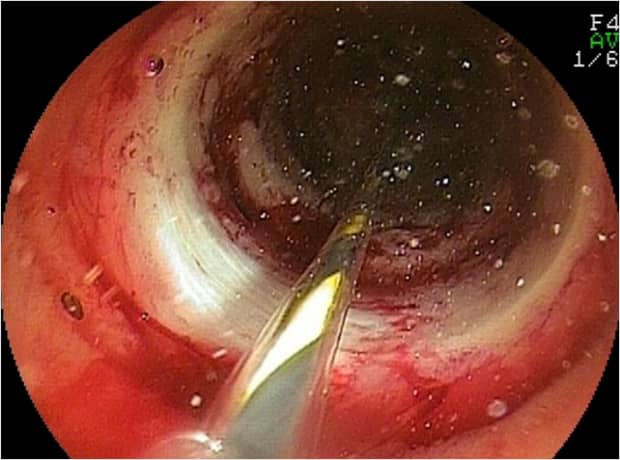

[ダブルバルーン小腸内視鏡画像]

狭窄部に対して内視鏡的拡張術の写真です.